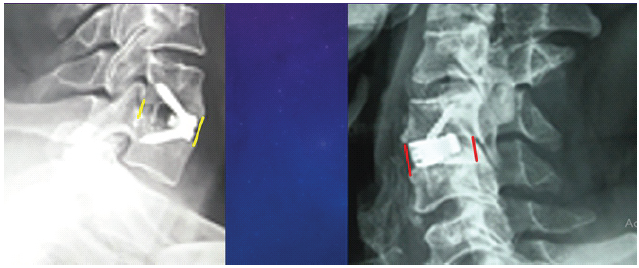

The FSDH in Group A increased from 5.5 ± 1.1 mm pre-operatively to 7.4 ± 1.4 mm post-operatively, then settled at 6.5 ± 1.2 mm at 1 year. Similarly, Group B showed an improvement in FSDH from 5.2 ± 0.7 mm pre-operatively to 7.8 ± 0.8 mm post-operatively, stabilizing at 7.2 ± 1 mm at 1 year. Cage subsidence was observed in 2 of 8 cases (25%) in Group A, while no subsidence was noted in Group B (Fig. 5a and b).

Figure 5: (a and b) Polyetheretherketone implant shows signs of subsidence (left) compared with the titanium implant (right).